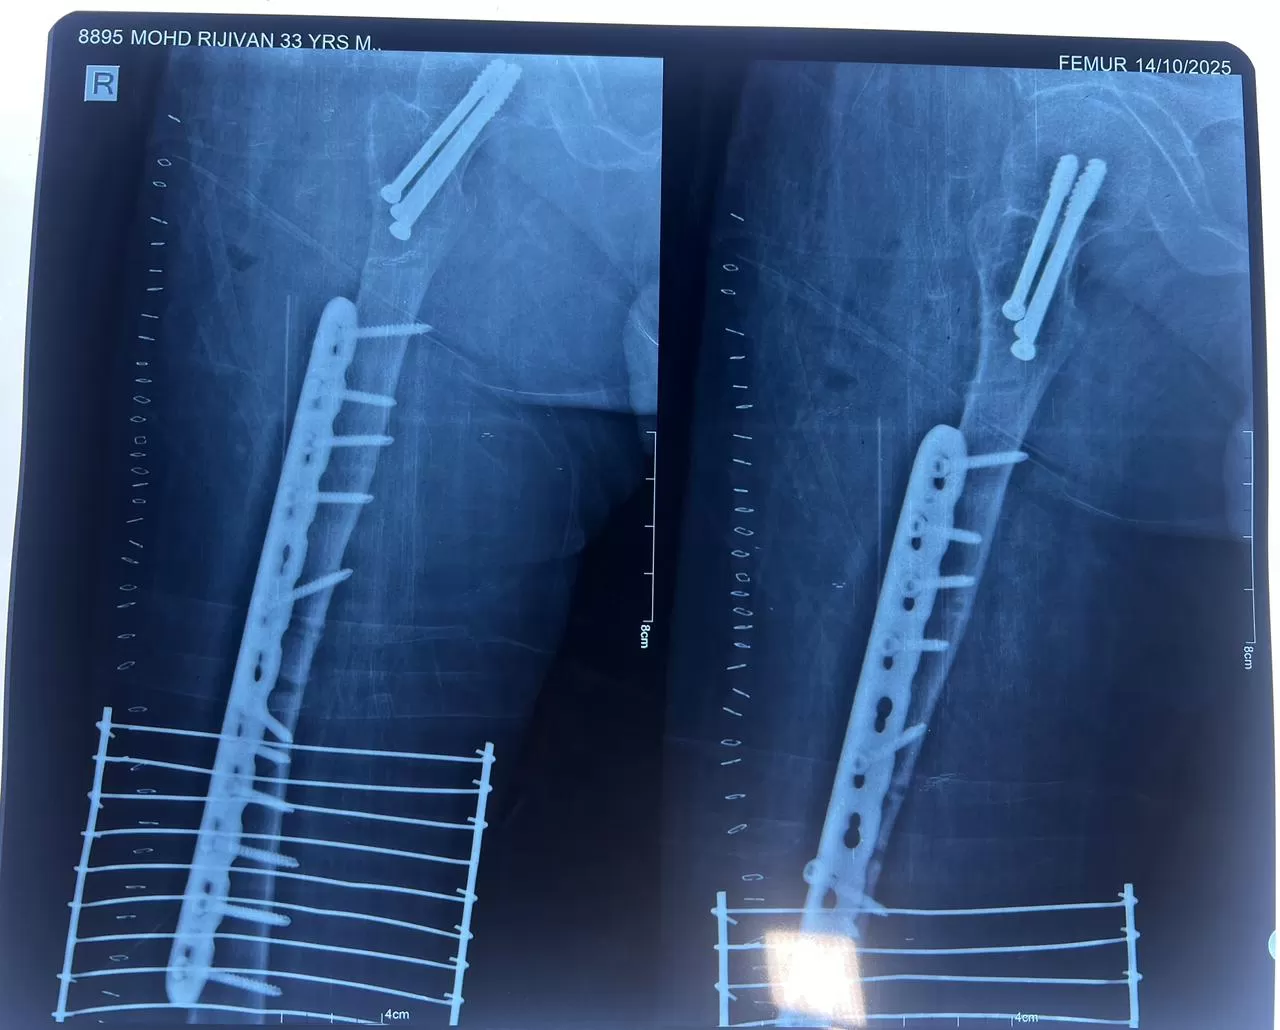

Rizwan

Name: Rizwan

Date of Operation: 13 October 2025

Age: 35 Years